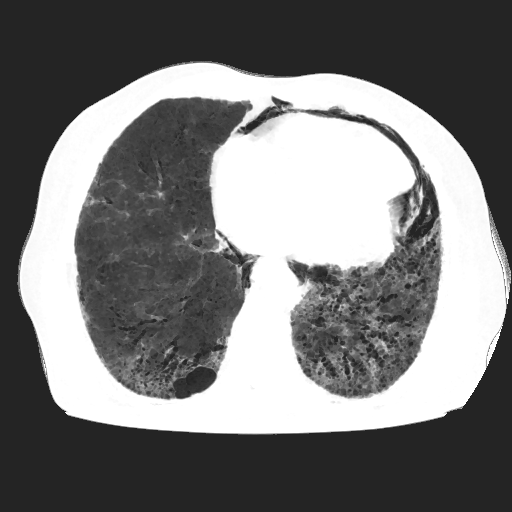

El parénquima pulmonar izquierdo muestra un infiltrado intersticial difuso que causa engrosamiento del septum axial, además del fenómeno de bronquiectasias quísticas se observan pequeñas bulas enfisematosas de localización subpleural que compromete ambas bases pulmonares.

Se observan imágenes de vidrio despulido en todo el lóbulo inferior izquierdo, el cual compromete los segmentos de la língula del segmento superior y medio

El parénquima pulmonar derecho muestra infiltrado intersticial en imagen de vidrio despulido con evidencia de lesiones subpleurales que representan bullas enfisematosas de diferentes tamaños.

Al utilizar un contraste Minip, se observan bronquiectasias cilíndricas en el extremo del lóbulo superior derecho, observándose un patrón de panal de abeja situada en la región apical del lóbulo superior izquierdo.

Bronquiectasias cilíndricas, bullas enfisematosas basales bilaterales